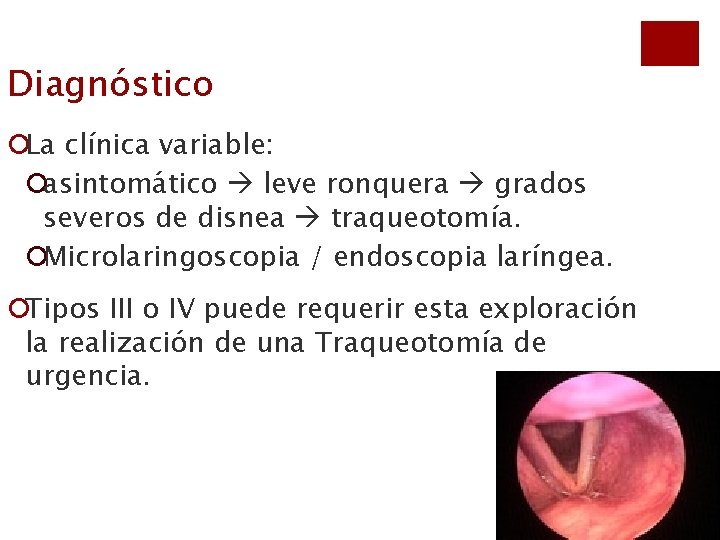

Diagnóstico ¡La clínica variable: ¡asintomático leve ronquera grados severos de disnea traqueotomía. ¡Microlaringoscopia / endoscopia laríngea. ¡Tipos III o IV puede requerir esta exploración la realización de una Traqueotomía de urgencia.